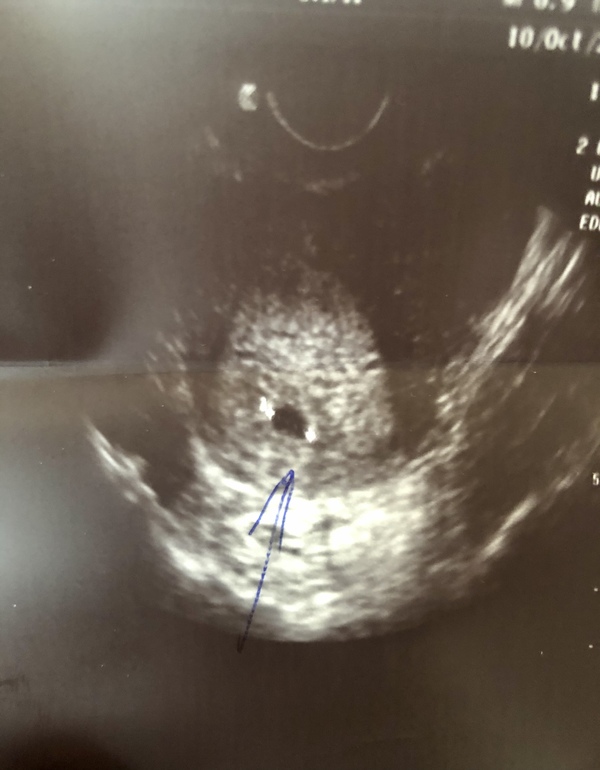

Была на узи,нашли ПЯ

Девочки,Нас нашли🙏Всё соответсвует сроку 5,1 неделя.ПЯ 9мм.☺️